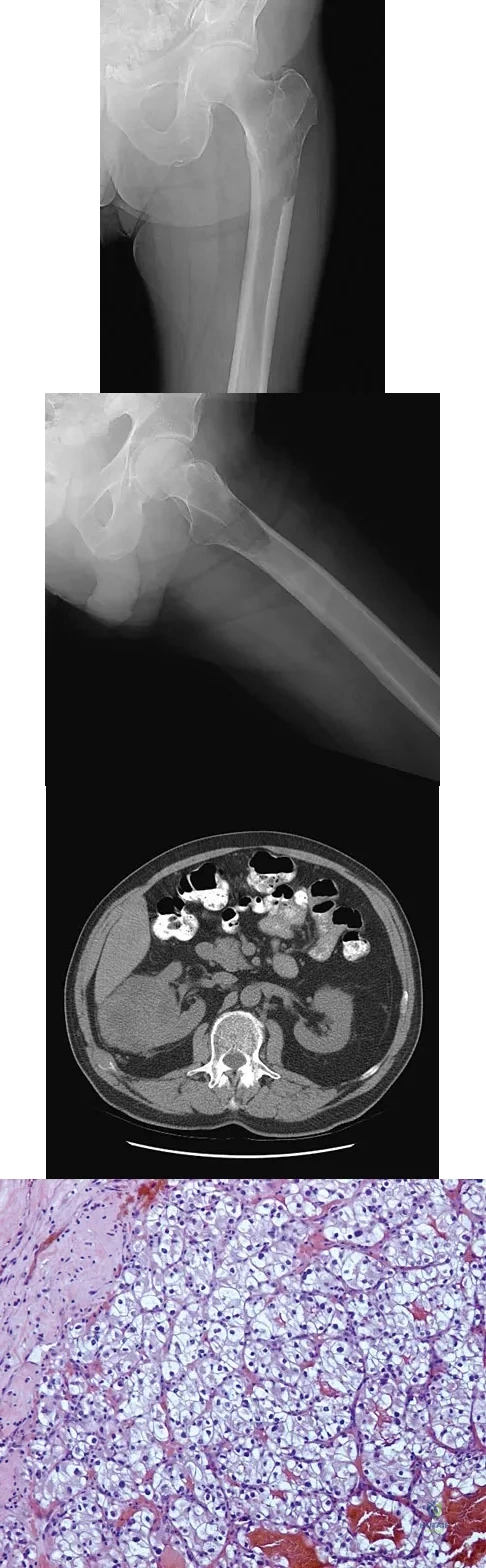

Question 87

A 25-year-old man has had an insidious onset of left hip pain over the past 11 months. A radiograph, coronal MRI scan, and histopathologic specimens are seen in Figures 2a through 2d. What is the most likely diagnosis?

Explanation